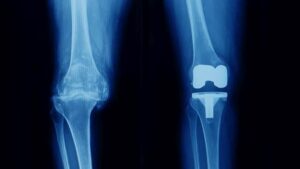

Al respecto, información de Orthoinfo refiere que la rodilla es la articulación más grande del cuerpo. Es necesario tener rodillas sanas para hacer la mayoría de las actividades diarias:

“La rodilla está compuesta por el extremo inferior del hueso del muslo (fémur), el extremo superior de la espinilla (tibia), y la rótula. Los extremos de estos tres huesos están recubiertos por el cartílago articular, una sustancia suave que protege los huesos y les permite moverse con facilidad en la articulación”.